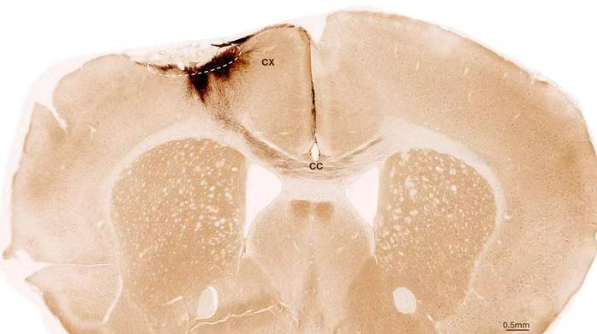

神经干细胞移植后小鼠大脑的冠状切面。虚线圆圈标示了中风区域。移植的人类细胞所发出的神经突起被染成深棕色。这些神经突起不仅向局部皮层(CX)延伸,还通过胼胝体(CC)延伸至另一侧大脑半球。图片来源:苏黎世大学